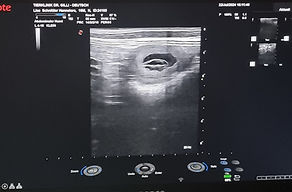

Lisa_Havaneser_2024-08-21_09-30-11_Abdomen_LL.jpg